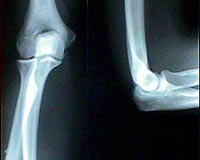

Researchers are developing technologies that use lasers to create arterial stents and longer-lasting medical implants that could be manufactured 10 times faster and also less expensively than is now possible.

New technologies will be needed to meet the huge global market for artificial hips and knees, said Yung Shin, a professor of mechanical engineering and director of Purdue's Center for Laser-Based Manufacturing.

The worldwide population of people younger than 40 who receive hip implants is expected to be 40 million annually by 2010 and double to 80 million by 2030. In addition to speeding production to meet the anticipated demand, Shin said another goal is to create implants that last longer than today's.

"We have 200,000 total hip replacements in the United States," he said. "They last about 10 years on average. That means if you receive an implant at 40, you may need to have it replaced three or four times in your lifetime."

One of the researchers' techniques works by depositing layers of a powdered mixture of metal and ceramic materials, melting the powder with a laser and then immediately solidifying each layer to form parts. Because the technique enables parts to be formed one layer at a time, it is ideal for coating titanium implants with ceramic materials that mimic the characteristics of natural bone, Shin said.

"Titanium and other metals do not match either the stiffness or the nature of bones, so you have to coat it with something that does," Shin said. "However, if you deposit ceramic on metal, you don't want there to be an abrupt change of materials because that causes differences in thermal expansion and chemical composition, which results in cracks. One way to correct this is to change the composition gradually so you don't have a sharp boundary."

The gradual layering approach is called a "functionally gradient coating."

Researchers used their laser deposition processes to create a porous titanium-based surface and also a calcium phosphate outer surface, both designed to better match the stiffness of bone than conventional implants.

The laser deposition process enables researchers to make parts with complex shapes that are customized for the patient.